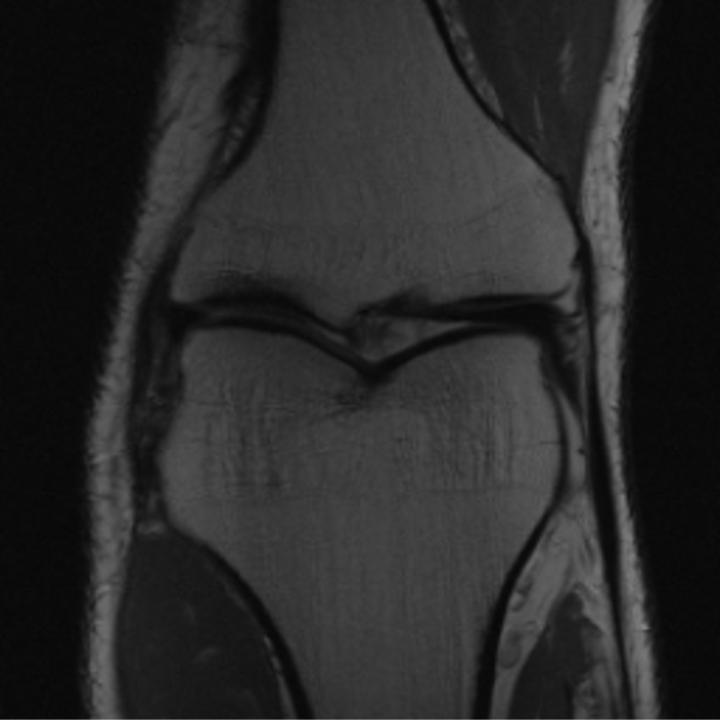

One way to test the generalization capability of the trained X-Diffusion is to test it on a completely different domain from an MRI dataset not seen during training. We report the single-slice results on the test set of knees from NYU fastMRI [33, 80], using the X-Diffusion trained on the BRATS brain MRIs. The test PSNR result is 34.17 and an example is shown in Figure 8. It shows how successfully X-Diffusion can generate knee MRIs (out-of-domain) despite being trained on brains.

Small Knee MRIs clinical study. To qualitatively assess how realistic our generated knee out-of-domain 3D volumes were (produced from a single slice), we gave 20 generated examples alongside their real MRI counterparts to an expert orthopedic surgeon J. F.. He was then asked to identify the real example from a set of 20 MRI pairs. The surgeon correctly identified the real MRI in only 10 out of 20 pairs, could not decide in 3 pairs, and misidentified the generated MRI as real in the remaining 7 pairs. This further validates the generated out-of-domain MRIs.